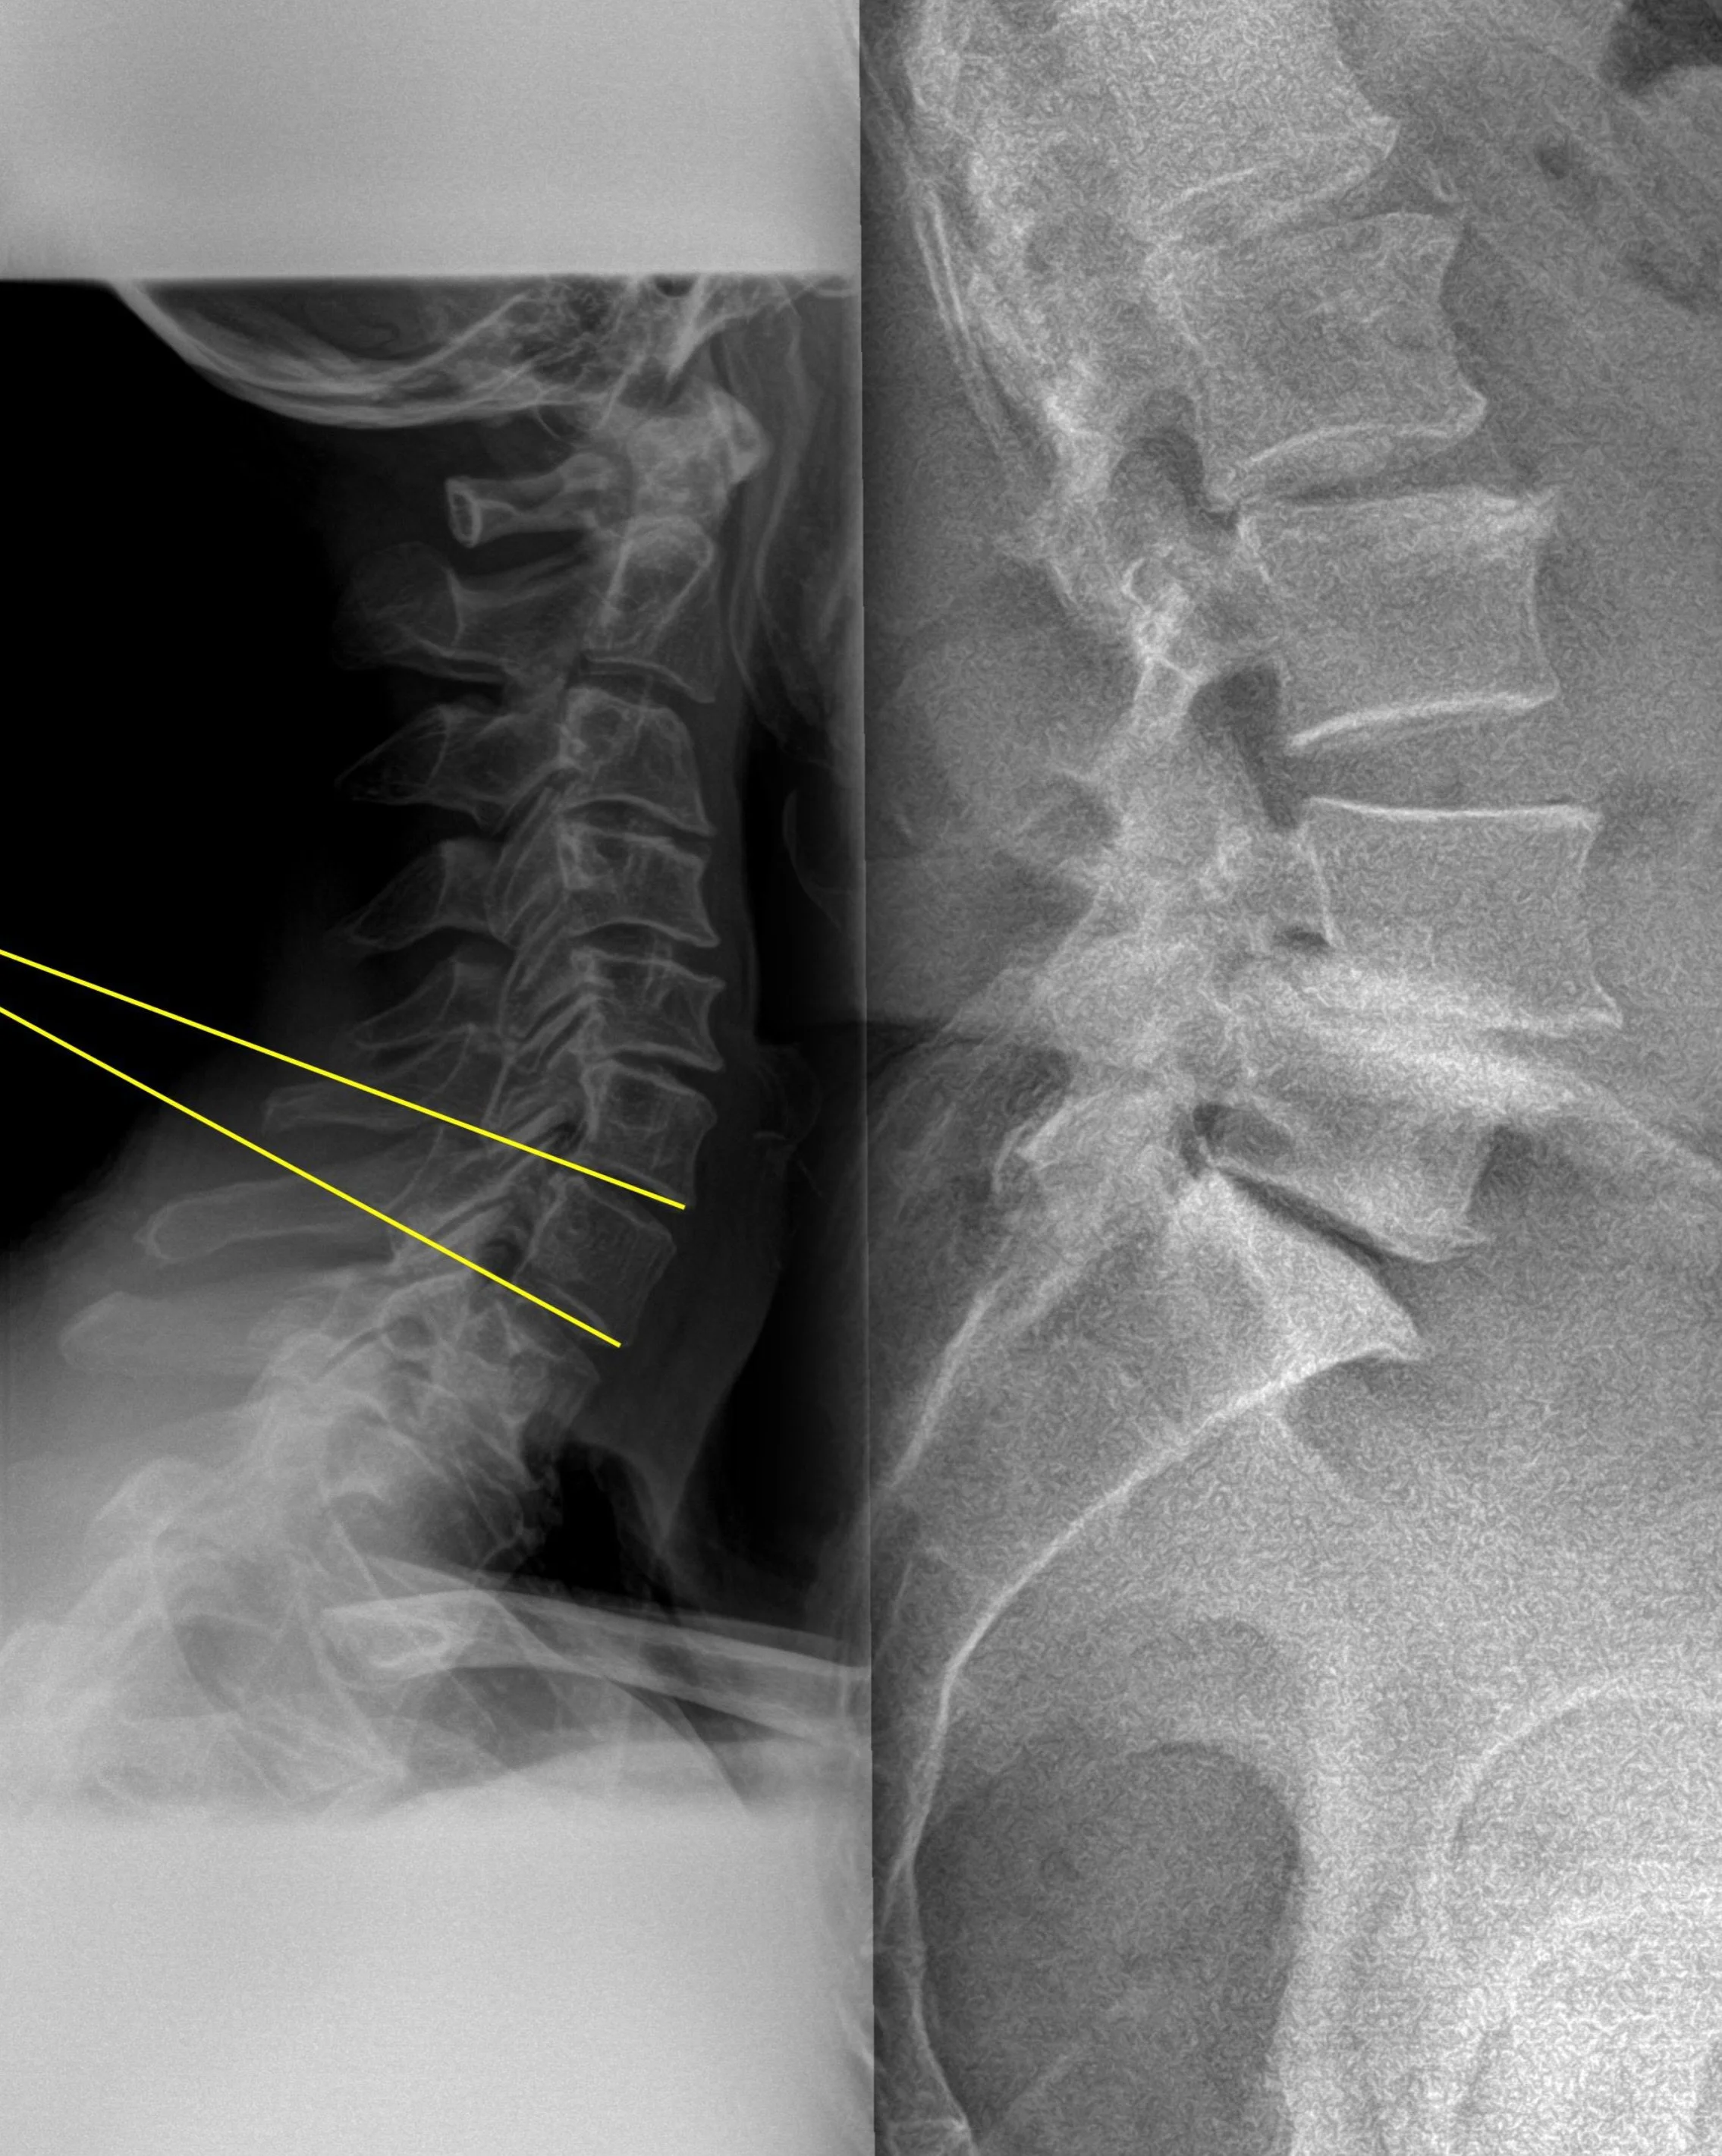

X-ray showing misalignment at lower lumbar and neck, likely caused by an old accident. Untreated, this can lead to arthritis — which is why we’re taking a proactive, collaborative approach

The lumbar X-ray showed misalignment and compression at the L4/L5 junction. While I haven’t experienced major symptoms thanks to consistent training, this could lead to arthritis or more serious complications if left untreated. The cervical image showed a loss of curve and alignment around C6, which could impact posture, nerve function, and movement control over time.